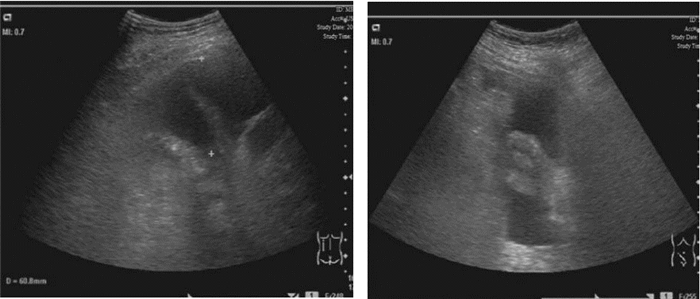

1 病例资料患者,女,64岁,因“反复膝关节疼痛伴腹胀全身肿胀2月余”入院。患者2个月前反复膝关节疼痛后渐出现腹痛腹胀及全身肿胀,及胸闷气急。10 d前至当地医院诊治,给予抗感染、抑酸,营养支持等对症治疗。患者症状无明显好转,遂至本院急诊。既往行“胆囊切除术”后2年,“鼻息肉切除术”后7个月。查体:BP 139/72 mmHg,P:88次/min,R:25次/min,T:37.5 ℃。嗜睡,精神软,口唇无发绀,皮肤干粗糙,巩膜无黄染,全身浅表淋巴结未触及肿大;两肺呼吸低,未闻及干湿性啰音;心率58次/min,律齐,心音低,未闻及病理性杂音;腹膨隆,未见腹壁静脉曲张,腹部可见一长约10 cm手术疤痕,愈合好。未见胃肠型,全腹,左下腹压痛、反跳痛,肝脾触诊不满意,麦式点无压痛,肠鸣音1次/分,腹部移动性浊音阳性;全身浮肿;生理反射存在,病理反射未引出。辅助检查:2012.9.5 肝功(本院):总蛋白 53.2 g/L,白蛋白 24 g/L,尿素 18.41 mmol/L,肌酐 154 μmol/L,血糖 8.74 mmol/L。2012.9.5急诊血常规白细胞 20.6×109/L,中性粒细胞 81.6%,血红蛋白 69 g/L,血小板 22×109/L 。急诊血气分析:pH 7.360,二氧化碳分压. 29.0 mmHg,氧分压. 126.0 mmHg,剩余碱.-8.0 mmol/L;2012.8.28 CT(当地医院)示:两侧胸腔积液伴两下肺压迫性肺不张,心包少量积液,腹腔盆腔积液,肝脏密度不均匀,脾脏增大(图 1,图 2)。2012.8.29 B超(当地医院)示:腹腔积液,双侧胸腔积液(图 3,图 4)。血补体C3 0.472 g/L(0.85~1.93),补体C4 0.077 g/L(0.12~0.36);血T3 0.28 μg/L(0.61~0.81),T4 13.60 μg/L (45~109),FT3 0.70 pmol/L(3.5~6.5),FT4 5.38 pmol/L(11.5~22.7)TSH6.67(0.35~5.50) TPOAb、TgAb阳性;血C-反应蛋白 36 mg/L;腹水外观血性混浊 李凡氏试验(+) 中心粒20 淋巴细胞50间皮细胞25,蛋白35 g/L,CA125 123 U/mL;风湿免疫功能:ANA,SCL-70,JO-1,U1RNP,SM,SS-A,SS-B,组蛋白抗体,抗线粒体抗体,抗PCNA抗体,板层素抗体,抗肌动蛋白抗体,着丝点抗体,抗核小体抗体,均阴性;凝血全套正常;结核抗体阴性;肿瘤指标CA125 512 U/mL。入院诊断为:原发性甲状腺功能减退、多浆膜腔积液。口服左甲状腺素片50 μg/d为初始剂量,以后逐渐增至150 μg/d,泼尼松5 mg早8:00、晚16:00 口服,患者3 d后食欲好转,查头颅MRI及血垂体功能检测正常,排除继发性甲减,停用泼尼松。半月后浮肿消退,至住院1月复查CA125 20 U/mL;B超:心包积液及双侧胸膜腔积液完全吸收,腹腔少量液性暗区。住院40 d复查甲功正常;B超:肝肾隐窝、脾周及腹腔内均未见游离液性暗区(图 4),临床痊愈,出院,出院后服用左甲状腺素片150 μg/d,定期随访,目前以此剂量维持。

| 图 2 治疗前B超:A 胸腔积液,B 腹腔积液 |